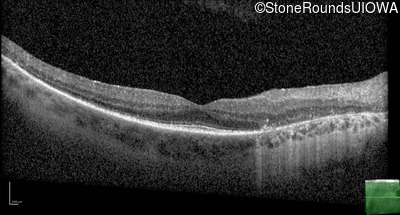

OCT Stack

20/30 -2